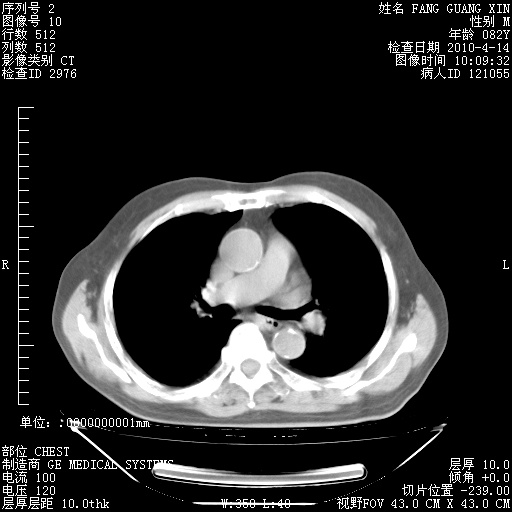

楼主| 发表于 2010-4-28 16:59 | 显示全部楼层

4月28日肺部CT——再次出现类似去年5月9日——透光度降低,(影像科认为)“间质性”改变。

1221483 1 .bmp

1221483 2 .bmp

1221483 3 .bmp

1221483 4 .bmp

1221483 5 .bmp